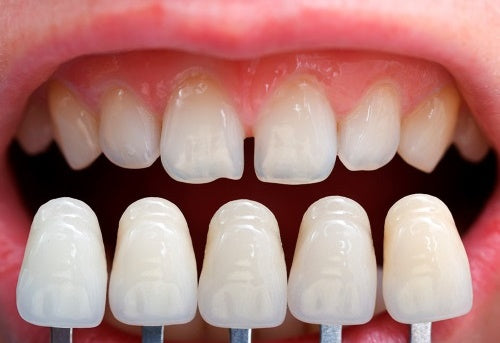

Les facettes dentaires représentent de fines coques de céramique qui viennent se coller définitivement sur les dents antérieures pour redonner aux patients un sourire parfait en corrigeant les anomalies de teintes, de formes et/ou d'alignement.